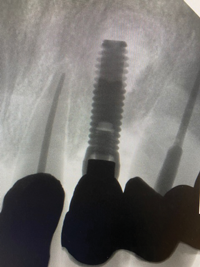

In this case, a dental implant that had been placed 10 years prior was functional, stable, and esthetically acceptable to the patient. However, a significant fistula was present on the facial-apical aspect of the ridge in the maxillary lateral incisor area. This area was painfully sensitive to touch and demonstrated purulence when squeezed. To evaluate the lesion, first, a conventional digital radiograph was acquired, which revealed an apical radiolucency at the apex of the implant (Figure 1). Further analysis using cone-beam computed tomography (CBCT) demonstrated a fistula from that site to the oral environment (Figure 2). Treatment options were discussed, including removal of the implant, followed by grafting, a healing period, and replacement of the implant and implant-retained crown. If this option was selected, a transitional appliance would need to be created. Another option was to attempt to salvage the implant and implant crown by treating the infection and grafting the site to create a new boney wall and eliminate the fistula. Ultimately, the patient accepted this option to attempt to salvage the fixture and crown.

(1.) Preoperative radiographic evaluation demonstrating a large radiolucency at the apical third of the body of an implant fixture replacing the patient’s maxillary left lateral incisor. The implant was stable, and the prosthesis was deemed esthetically acceptable by the patient.

Figure 1